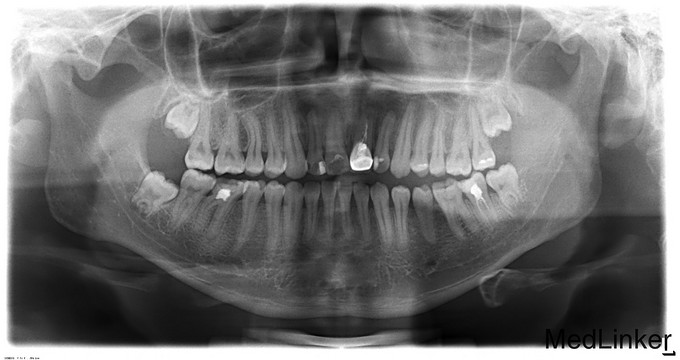

正颌术后半年要求取出钛板

双侧面部基本对称,张口度3.5cm,张口型“↓”,双侧髁突动度正常,张闭口未闻及关节弹响。口内检查:双侧下颌前庭沟可见手术瘢痕。左下6颊侧可见一瘘管,轻压痛,无溢脓。36牙合面大面积充填物,46残冠。双侧头颈淋巴结未触及明显异常。

诊断:1.双侧下颌正颌术后钛板存留2.36、46残冠,全麻下行双侧下颌骨钛板取出术+双侧下颌骨邻近瓣转移修复术+36、46拔除术,手术经过顺利,麻醉满意,术后予消炎、消肿等对症治疗。